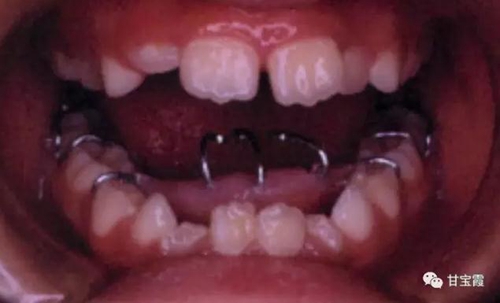

家長(zhǎng)發(fā)現(xiàn)孩子嘴型不好看,吃東西也咬不斷,就帶著孩子找我看診,經(jīng)過(guò)檢查和診斷,我決定給孩子戴個(gè)舌刺,讓孩子的舌頭舔不著下前牙,如下圖

一個(gè)半月后復(fù)診檢查發(fā)現(xiàn)前牙反頜和開(kāi)合都有所好轉(zhuǎn)

舌刺戴用五個(gè)半月后孩子的前牙就能咬上了。所以作為家長(zhǎng)要關(guān)注孩子的牙齒,一旦發(fā)現(xiàn)異常就及早請(qǐng)正畸醫(yī)生看診,早發(fā)現(xiàn)早治療,花錢(qián)少效果好。